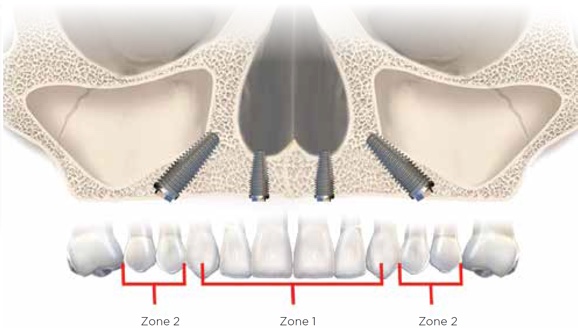

Radiographic evaluation of the edentulous maxilla is necessary for determining whether axial, tilted, or zygomatic implants would be indicated to establish optimal posterior support with proper anterior-posterior distribution of implants for a fixed prosthesis. Because the edentulous maxilla is divided into three radiographic zones, a systematic assessment of the residual alveolar bone available for implant placement can be made. In this pretreatment screening protocol, the alveolar bone supporting the maxillary anterior teeth is designated as zone 1, while the premolar region is considered zone 2 and the molar region zone 3 (Figure 4). Analysis of the radiographic results according to this scheme can enable the surgical and restorative team to devise a preliminary treatment plan. In complex situations, 3-dimensional (3D) radiographic evaluation may still be necessary to confirm the preliminary conclusions.

Evaluation of the various zones of the maxilla will guide the surgical team in determining the type of surgical approach to take for placement of implants. Use of panoramic scout film as well as 3D radiography to evaluate the zones will help the surgeon understand the quantity of bone available for each intended implant site.

For patients in whom alveolar bone is present in all three zones of the edentulous maxilla, conventional implants may be placed (Figure 5). This should allow for a favorable arch form of anterior, posterior, and possibly intermediate implants for a fixed prosthesis.8,9

Fig 4. The zones of the maxilla.

Figure 4

Fig 5. Axial implant placement, with presence of bone in zones 1, 2, and 3.

Figure 5